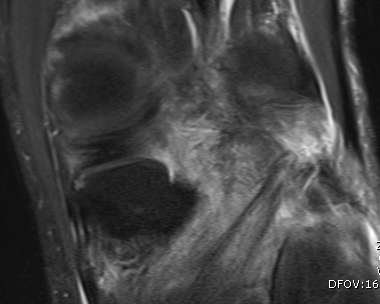

MRI

Popliteus anatomy

Don't see entire length on single images

- coronal image to see insertion onto popliteal fossa below LCL

- follow tendon around on coronal images

- watch as becomes musculo-tendinous (can often be torn here)

- muscle inserts onto posteromedial tibia

Popliteofibular ligament anatomy

Normal anatomy

Injury

Femoral avulsion of popliteus and LCL

Femoral avulsion of popliteus

Avulsion of LCL and biceps femoris from fibula head

Musculotendinous injury to popliteus